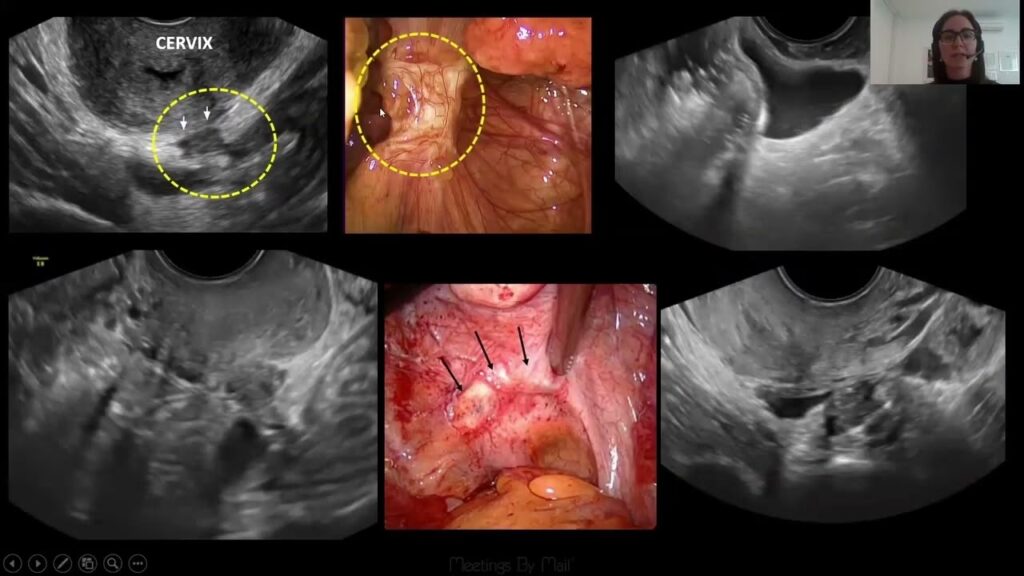

Transvaginal ultralyd

En specialiseret transvaginal ultralyd, udført af en erfaren sonograf eller læge, er et utroligt effektivt værktøj. Den har vist sig at have en sensitivitet og specificitet på over 90% for at opdage dyb infiltrerende endometriose og endometriomer. Under undersøgelsen vurderes ikke kun livmoderen og æggestokkene, men også de forreste og bageste rum i bækkenet. Lægen kan dynamisk vurdere organernes bevægelighed og identificere specifik ømhed. Et vigtigt tegn er det såkaldte "sliding sign". Hvis endetarmen og livmoderen ikke glider frit mod hinanden, indikerer det en sammenvoksning af fossa Douglasi, hvilket er afgørende information for en kirurgisk planlægning.

I mange år blev diagnostisk laparoskopi betragtet som den absolutte "guldstandard" for at stille diagnosen endometriose. Dette er en kirurgisk procedure, hvor en kirurg laver små snit i maven og indsætter et tyndt rør med et kamera (et laparoskop) for direkte at visualisere bækkenorganerne. Kirurgen kan se endometriose-læsionerne, vurdere deres omfang og tage vævsprøver (biopsier) til mikroskopisk analyse for at bekræfte diagnosen.